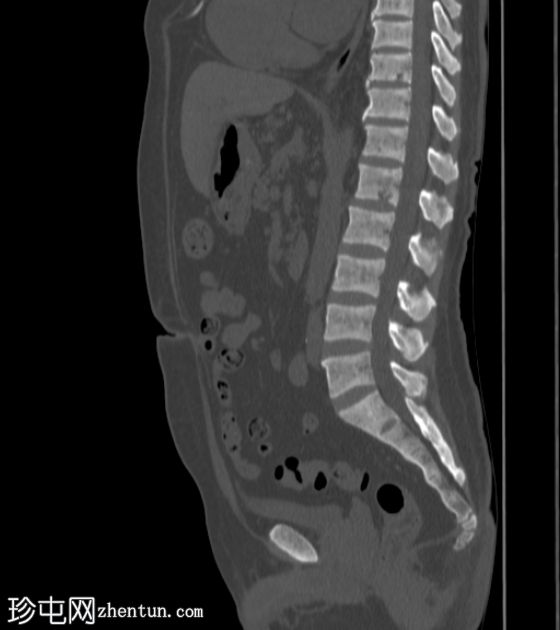

矢状位

骨窗

8.jpg

再次显示双侧肾囊性疾病,可见多个复杂(出血性)囊肿,以及与左肾上极复杂出血性囊肿相连的左肾周血肿。左肾周脂肪间隙模糊。

双侧多发性小肾结石。

弥漫性骨硬化,提示肾性骨营养不良。